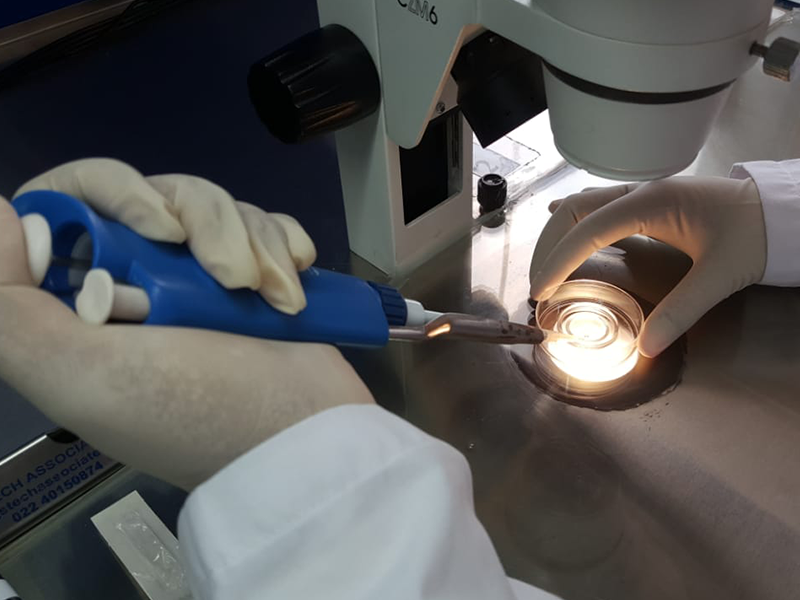

Hands-on guidance in micromanipulation, embryo handling, laboratory protocols, and quality control aligned with international IVF lab standards.

Focused on laboratory protocols, equipment handling, and workflow management, our IVF lab specialists ensure trainees understand precision, consistency, and accuracy in daily ART lab operations.

Specializing in advanced micromanipulation techniques, this mentor supports skill development in procedures such as ICSI and related laboratory practices with hands-on guidance.